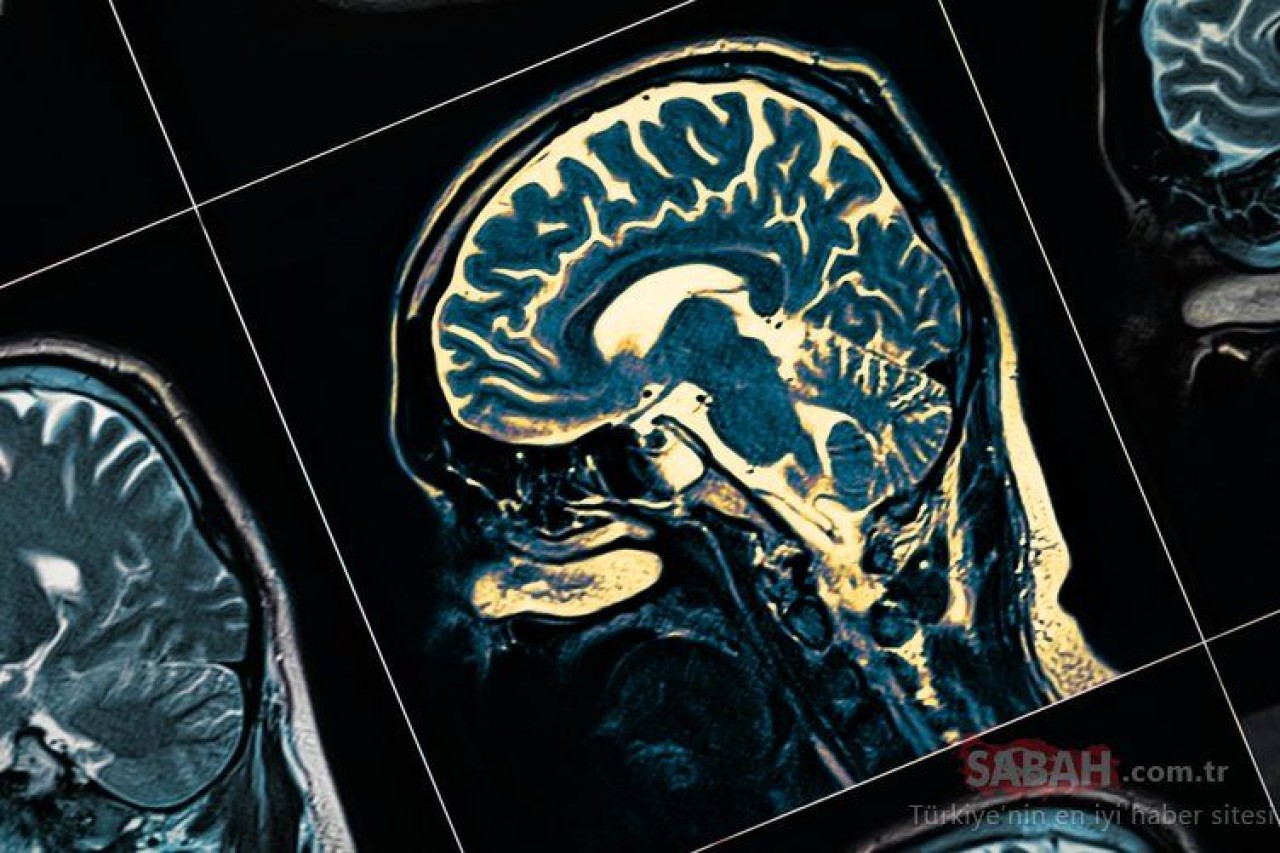

Peki, B12 vitamini eksikliğinin belirtileri nelerdir? B12 vitamin eksikliğini gideren besinler nelerdir? İşte B12 vitamin eksikliğinin ilk belirtileri ve B12 vitamin deposu besinler...İç Hastalıkları Uzmanı Dr. Kamuran Kaya, B12 vitamininin alınamaması durumunda sinir sistemi ve beyinde ciddi ve kalıcı hasarlar oluşabileceğini söyledi.

Bu durum, sinir sistemi ve beyinde ciddi ve kalıcı hasara yol açabilir. Tedavi edilmeyen ve ciddi boyuta ulaşana kadar fark edilmeyen B12 vitamini eksikliği kişide derin depresyona, paranoya ve sanrılara, hafıza kaybına, idrar kaçırma ile tat ve koku kaybına dahi yol açabilmektedir.